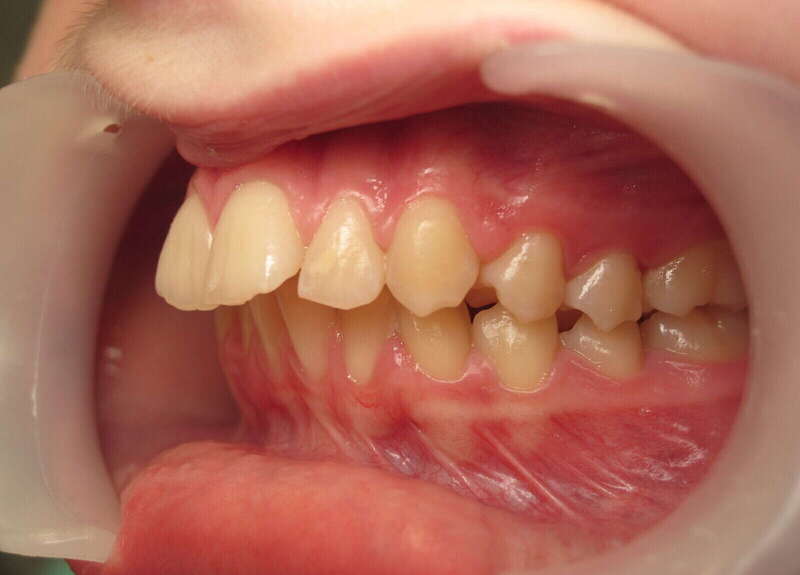

Ce cas d’interception chez un enfant de 8 ans démontre l'efficacité des aligneurs pour corriger des troubles fonctionnels précoces. Le diagnostic présentait des inversions d'articulé provoquant une déviation de la mandibule vers la gauche et un décalage des milieux.

Grâce à une coopération exemplaire et un traitement totalement indolore, l'expansion de l'arcade a permis de recentrer la mâchoire. Cette intervention a littéralement remis la croissance sur les rails, neutralisant le risque d'asymétrie faciale squelettique.

• Correction fonctionnelle : Recentrage immédiat de la mandibule et des milieux inter-incisifs.

• Prévention : Création d'un environnement favorable pour les dents définitives à venir.